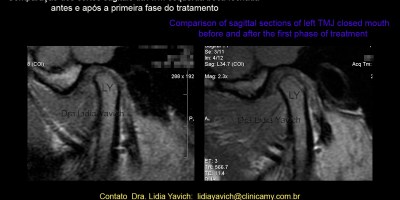

Tratamento Neuromuscular Fisiológico em Paciente com Cefaleia Diária e Dor nas Articulações Temporomandibulares. Caso Clínico sem Possibilidade de Recaptura Discal: primeira e segunda fase.